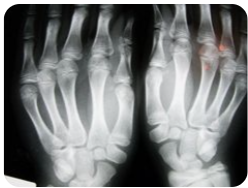

본비론 주사는 임상 연구에서 골밀도 증가 및 골절 예방 효과가 입증되었습니다.

특히 요추(허리뼈)와 대퇴골(엉덩이뼈)의 골밀도를 개선하는 데 탁월하며, 투여 후 약 6개월부터 효과가 나타나기 시작합니다.

또한 폐경기 여성에게서 흔히 나타나는 호르몬 변화로 인한 골 손실을 완화하며, 장기간 투여 시 골절 위험을 절반 이하로 줄이는 효과도 보고되었습니다.